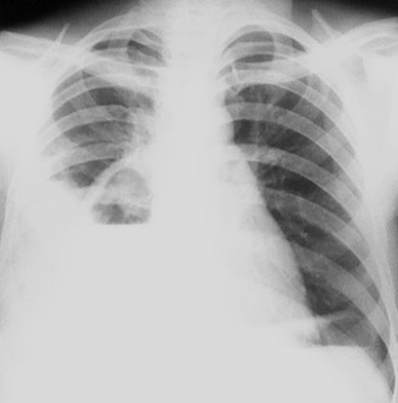

Rx toracică, incidență P-A

DESCRIERE:

la niv. întregului hemitorace stg → opacitate extinsă, nesistematizată, de intensitate mare, omogenă

caracter retractil → tracționează traheea și mediastinul de partea afectată

fără bronhogramă aerică

duce la micșorarea spațiilor intercostale

la niv. hemitoracelui controlateral → hipertransparență compensatorie

DX: atelectazie prin NBP central endobronșic (pe bronhia principală stg)

DD: pleurezie masivă → caracter expansiv